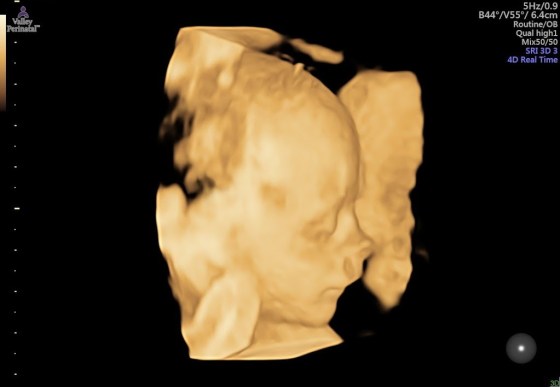

And last but not least, pictures of baby brother! Isn’t he already cute??